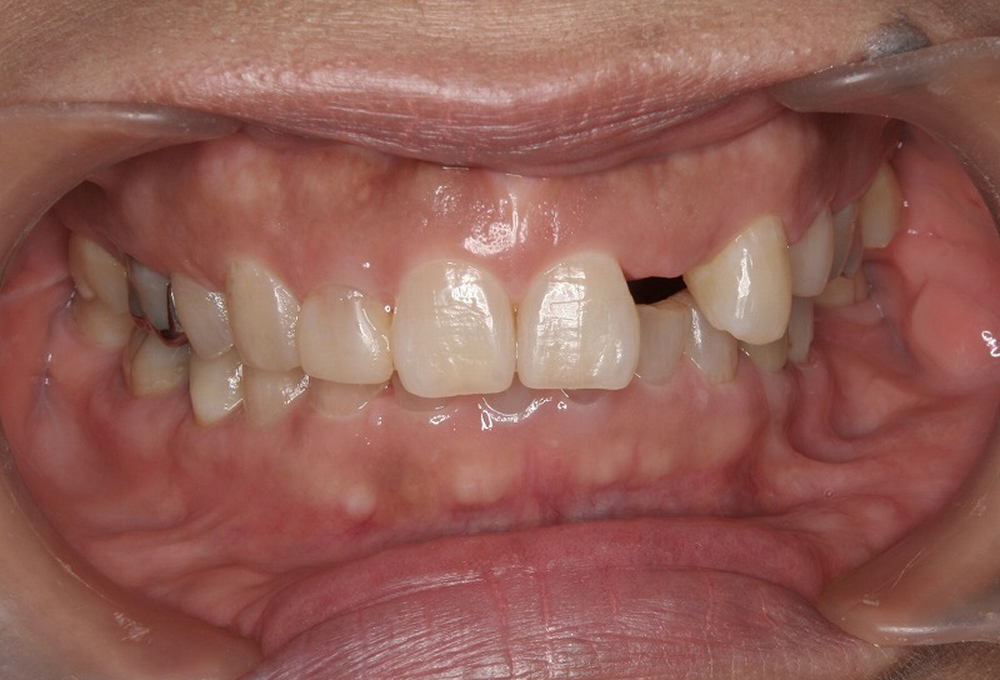

①術前